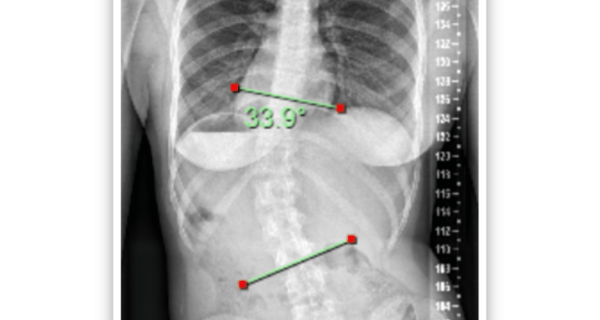

What are the typical postural habits of adolescents with idiopathic scoliosis (AIS)? And, are there any that are actually ‘typical’ at all? While it’s imperative we always look at the data and science, sometimes we have to remember that we are healthcare professionals with clinical experience and so much observation in day-to-day practice that often doesn’t get reported in scientific trials.

While of course every child is different and we cannot put each curve classification into a separate basket of behaviors, I thought I would share some typical clinical observations I have seen in these patients.